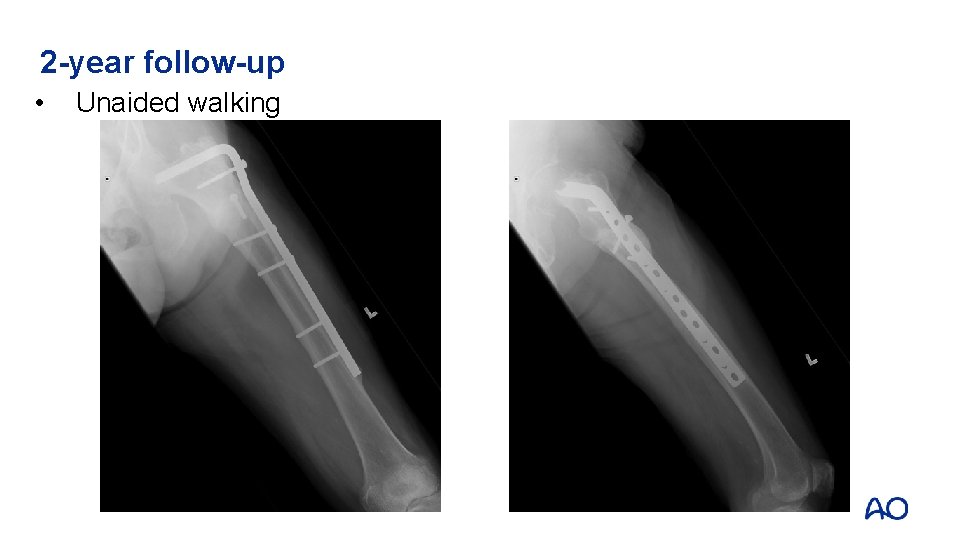

2 -year follow-up • Unaided walking